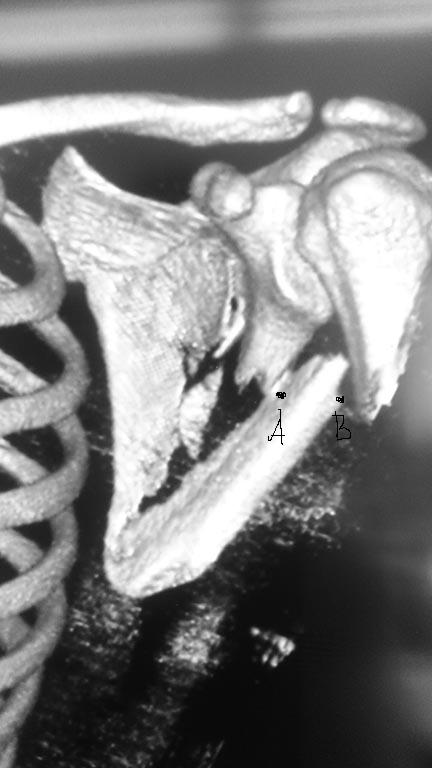

На рентгенограммах в прямой проекции или на 3D в прямой проекции

проксимальный фрагмент лопатки (вместе с гленоидом) выглядит смещенным к

средней линии т.е. медиализированным. На самом деле это ложная

медиализация, смещается нижний фрагмент лопатки латерально. Смещение его

более чем на 10мм (расстояние от т.А - латеральный край проксимального

отломка до точки В - лат. край дистального отломка)является показанием к

операции.